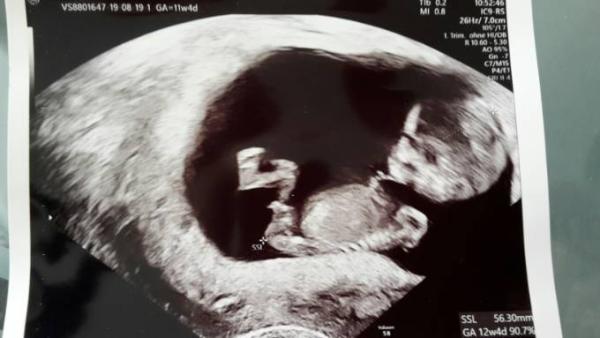

Komme gerade vom Termin und bin super erleichtert. Mein Hämatom ist nur noch minimal vorhanden. Das ganz tolle, ich darf ab Montag endlich mal wieder auf Arbeit. Mir fällt hier langsam auch die Decke auf den Kopf. .. Meinem Baby geht's super. Springt, hüpft, winkt. Alles super. Eigentlich sind wir heute 11+4, laut US aber schon bei 12+4. Und wir sind prima gewachsen 5,6cm. Ich bin glücklich. Der Tag ist gerettet.

Bild zu Heute FA - Forum für April - Mamis